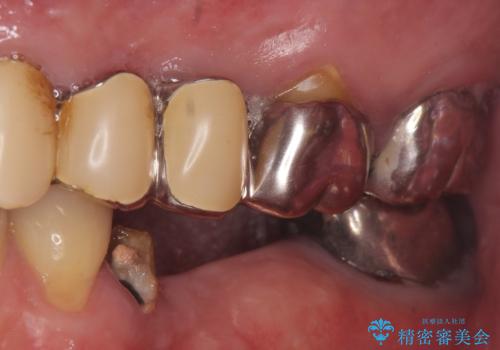

- 左下奥歯が虫歯で抜歯になってしまったため、インプラントにしたいといらっしゃった方の症例です。

欠損部位である左下5、6番目にインプラントを埋入し、オールセラミッククラウンによる補綴を行いました。

左下7番目は再根管治療を行い、オールセラミッククラウンによる補綴を行いました。